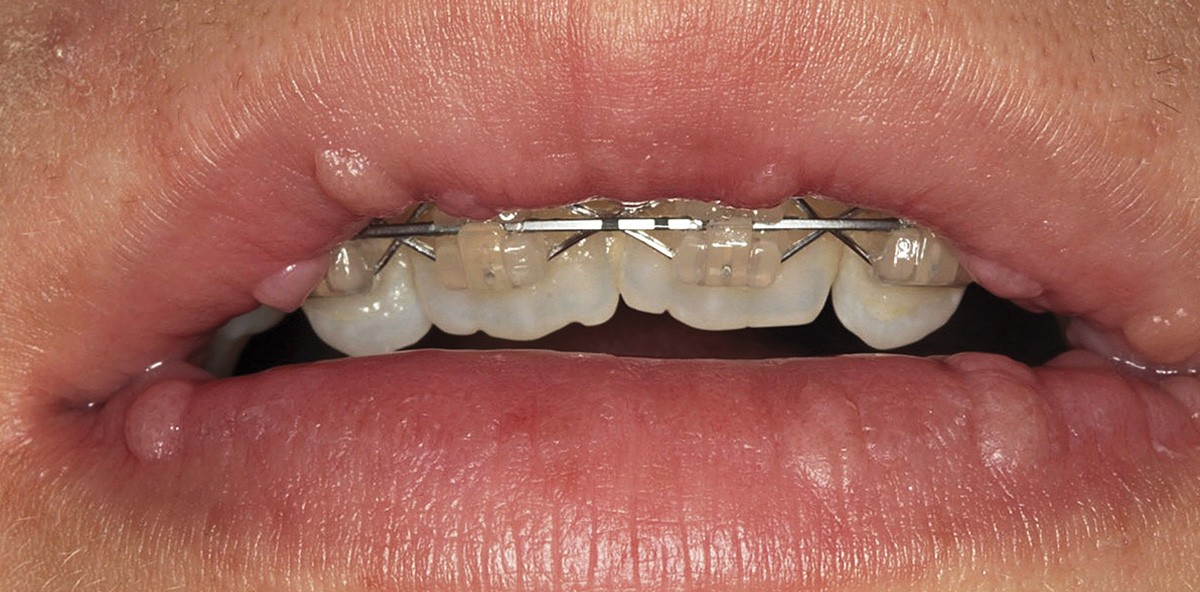

Die intraorale Manifestation zeigt parallel zu den Verhornungsstörungen schwere entzündliche Veränderungen am Zahnstützgewebe, schon kurz nach dem Durchbruch der Milchzähne. Es kommt zu akuten Entzündungen der Interdentalpapillen und der marginalen Gingiva, die zur Bildung von Zahnfleischtaschen führen, aus denen sich Pus entleert. In kurzer Zeit entwickelt sich eine Parodontitis marginalis profunda, die je nach Ausprägungsgrad des Syndroms zu einem Ausfallen der Milchzähne bis zum vierten oder fünften Lebensjahr führt.58 Im zahnfreien Intervall zwischen dem Verlust der Milchzähne und dem Durchbruch der bleibenden Zähne ist die Alveolarmukosa weitgehend unauffällig. Nach Durchbruch der bleibenden Zähne wiederholt sich der oben beschriebene parodontale Destruktionsprozess, sodass auch die bleibenden Zähne bis zum 15. Lebensjahr verloren gehen. Die Weisheitszähne bleiben verschont.52,58 Röntgenaufnahmen zeigen analog zum klinischen Befund massive Osteolysen der alveolären Knochenstrukturen.59